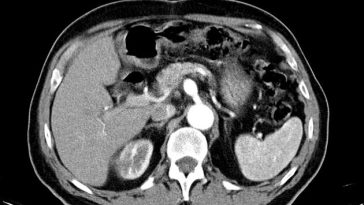

Breakthrough Lifesaving Intervention for Ruptured Celiac Artery Aneurysm

Modern Perspectives on Treating Celiac Artery Aneurysms The field of vascular surgery has seen remarkable progress over recent years, and few areas illustrate this advancement better than the successful minimally invasive treatment of ruptured celiac artery aneurysms. This opinion editorial offers an in-depth discussion of the current state of affairs, drawing upon a recently reported […] More